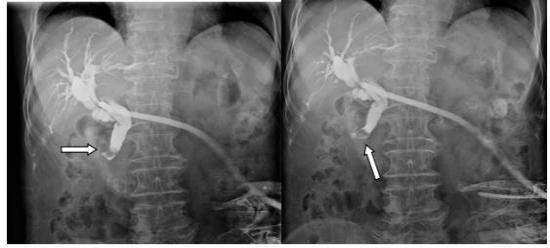

图1:右箭头示胆总管末端鸟嘴样狭窄;胆囊术后缺如,胆系扩张,少量造影剂进入十二指肠内。

图2:下箭头示胆总管下端充盈缺损,其形态、位置、大小固定,边缘光整。